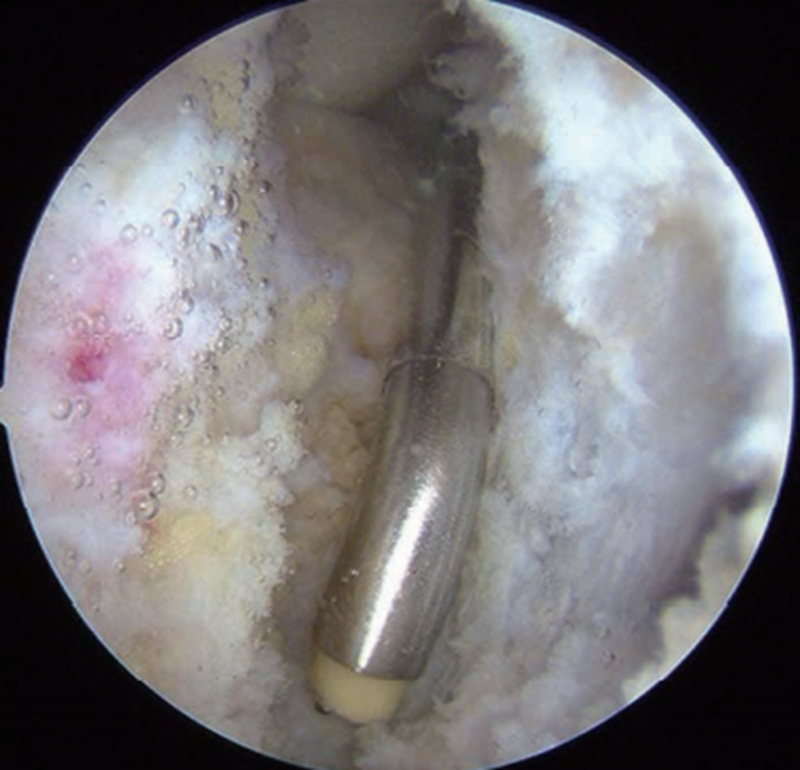

2.制备股骨隧道

从距离髌腱外侧1.5~2.0cm的远前外侧关节镜入路(图2)直视下定位股骨隧道内口。早期文献中PCL股骨选点通常偏前外束止点中心,大约位于股骨髁时钟11点位置(图3 A),距离软骨边缘7~8mm。为了在更偏等长位重建PCL,有研究更倾向于将股骨隧道定位点置于前外束与后内束交界部位,大约位于股骨髁10点30分位置,相当于e点(图3 B、C,图4)。打入定位导针确定位置无误后,制备与移植物同直径隧道。使用界面钉固定移植物时可选择由外向内制备股骨隧道的方法,更利于控制隧道方向和出入口位置。此方法可尽量避免股骨外侧髁软骨损伤,界面螺钉从股骨隧道内口挤入固定移植物。确实需要从内向外制备股骨隧道时(如使用Endobutton需阶梯隧道),采用远前外侧入路比距离髌腱外侧0.5cm的普通外侧入路能使股骨隧道的内口和外侧骨皮质的出口位置更可控(见图2)。

图3 PCL单束重建

A.股骨前外束定位点,远前外侧入路下直视定位,选择前外束(髁间窝11点位置)作为股骨隧道内口定位点;B. 股骨定位点,远前外侧入路下直视定位,选择前外束与后内束交界部位(髁间窝10点30分位置)作为股骨隧道内口定位点;C. 股骨等长定位点,PCL在股骨内侧髁上的止点范围扇形划分为a、 b、 c、 d、 e、 f 6个点,其中e点(髁间窝10点30分位置)与PCL胫骨止点之间最接近等长

图4 PCL单束重建股骨等长定位点示意图(A、B)和测试(C)

[资料来源:KOSUKE O, et al. Measurements of length and tension patterns duringreconstruction of the posterior cruciate ligament. Am J Sports Med, 1992, 20(3):351-355.]